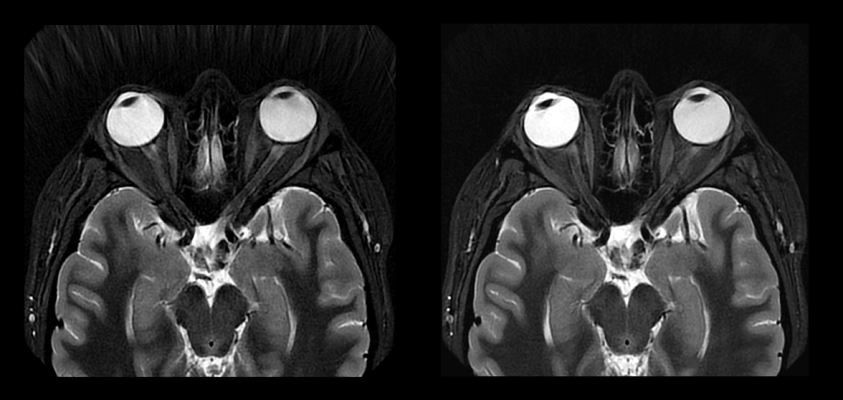

Additionally, AIR Recon DL is now compatible with PROPELLER, a motion-insensitive imaging sequence particularly important for anatomies susceptible to motion such as respiration during MRI exams, as well as pediatric, neurodegenerative, geriatric, and claustrophobic patients who have difficulty remaining physically still for the duration of an MRI scan. As a result, physicians can get sharper images without the need for repeat scans – translating to faster patient throughput, improved scheduling, shorter exam time, and faster diagnosis, helping to create an all-round better patient experience.

As of September 2022, at least 3.5 million patients globally have been scanned with AIR Recon DL. According to a recent AIR Recon DL 3D and PROPELLER reader study:

- 100% of the participants said that the deep learning solution provides better signal-to-noise ratio and better or equivalent image sharpness than conventional image reconstruction;

- 99% also said AIR Recon DL provides better or equivalent lesion conspicuity; and

- Reports also indicate up to 50% reduction in exam times, creating efficiency in workflow and increased productivity[2].

“By expanding AIR Recon DL to 3D and PROPELLER, GE Healthcare has closed the gaps in our ability to provide improved image quality and patient experience to all our patients across exam types, particularly for brain imaging where we rely heavily on 3D sequences and musculoskeletal imaging where PROPELLER is important for reducing image quality variability and eliminating repeat sequences due to motion,” says Dr. Tiron Pechet, Radiologist and Assistant Medical Director at Shields Health Care Group.